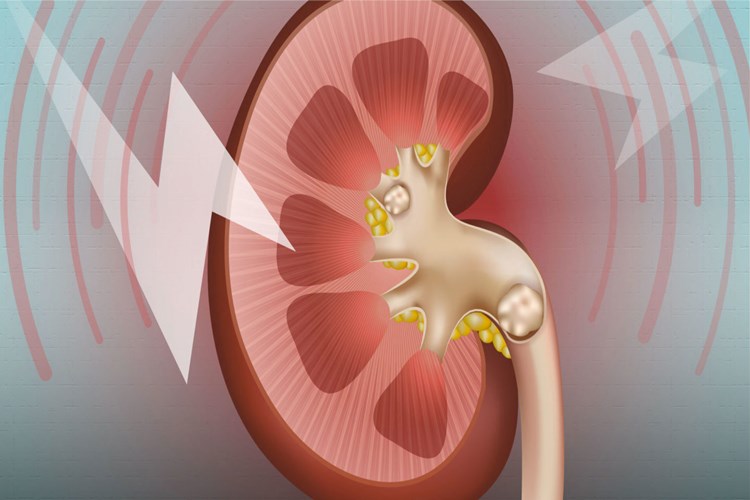

Ceviz tüketimi böbrek taşı oluşumuna neden olmaz, aksine

böbrek taşı oluşumunu önleyebilir. Ceviz, lif, protein, vitamin ve mineral

açısından zengin bir besindir ve içerdiği magnezyum, potasyum ve kalsiyum

mineralleri sayesinde böbrek sağlığına faydalıdır.

Böbrek taşı oluşumu, genellikle idrarda yüksek

konsantrasyonda bulunan minerallerin kristalleşmesi sonucu oluşur. Bu

kristaller, zamanla birleşerek küçük taşlar oluşturabilirler. Böbrek taşı

oluşumuna neden olan mineraller arasında kalsiyum, oksalat ve ürik asit

bulunmaktadır.

Ceviz, yüksek magnezyum içeriği sayesinde, kalsiyum oksalat

taşlarının oluşumunu önleyebilir. Ayrıca, ceviz tüketimi böbrek sağlığına faydalı

olacak diğer minerallerin de alınmasına yardımcı olabilir.

Bu nedenle, ceviz tüketimi böbrek taşı oluşumuna neden

olmaz, aksine sağlıklı bir beslenme düzeni içinde düzenli olarak tüketilmesi

böbrek sağlığına fayda sağlayabilir.